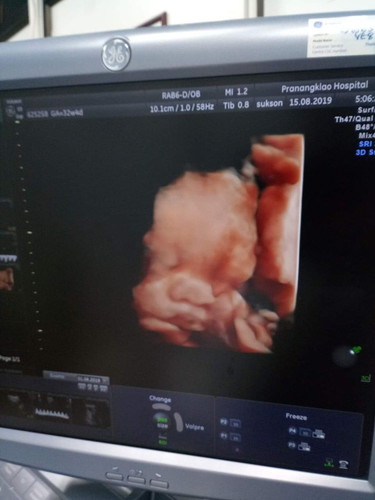

32 w ลูกตัวเล็ก

32 weeks พึ่งซาวเห็นหน้า ซาวทุกครั้งไม่ให้เห็นเลย ดีใตนะที่ได้เห็นแต่หมอบอกว่าลูกตัวเล็กไป.หนัก แค่1300เองค่ะ กินใข่ไม่ค่อยได้ แม่คนไหนมีวิธีไหนเพิ่มน้ำหนักได้ไหมค่ะที่ไม่ใช่การกินใข่ อ่ะ ค่ะ ช่วยแนะนำหน่อยนะค่ะ